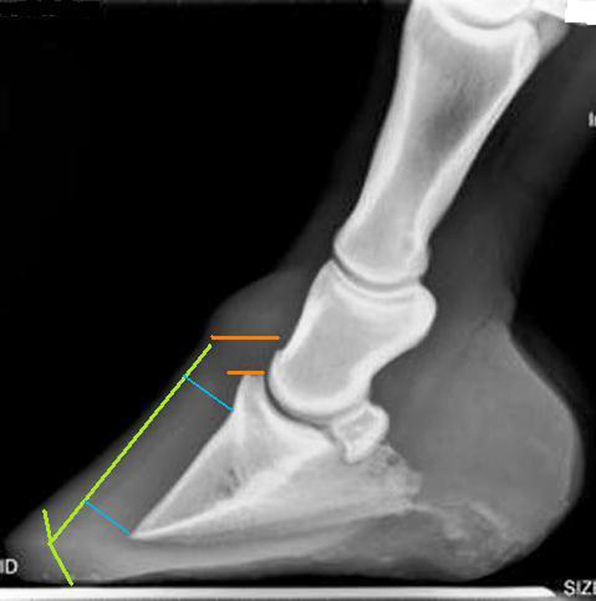

Radiographs in photo 3 confirmed the long toe flare which perpetuated the capsular rotation (green lines). The degree of separation between the coronet band and the extensor process (orange lines) demonstrates a moderate amount of distal descent. It is probable that the diminished support by the out-of-balance hoof capsule in relation to the coffin bone was enough to allow the bony column to descend.